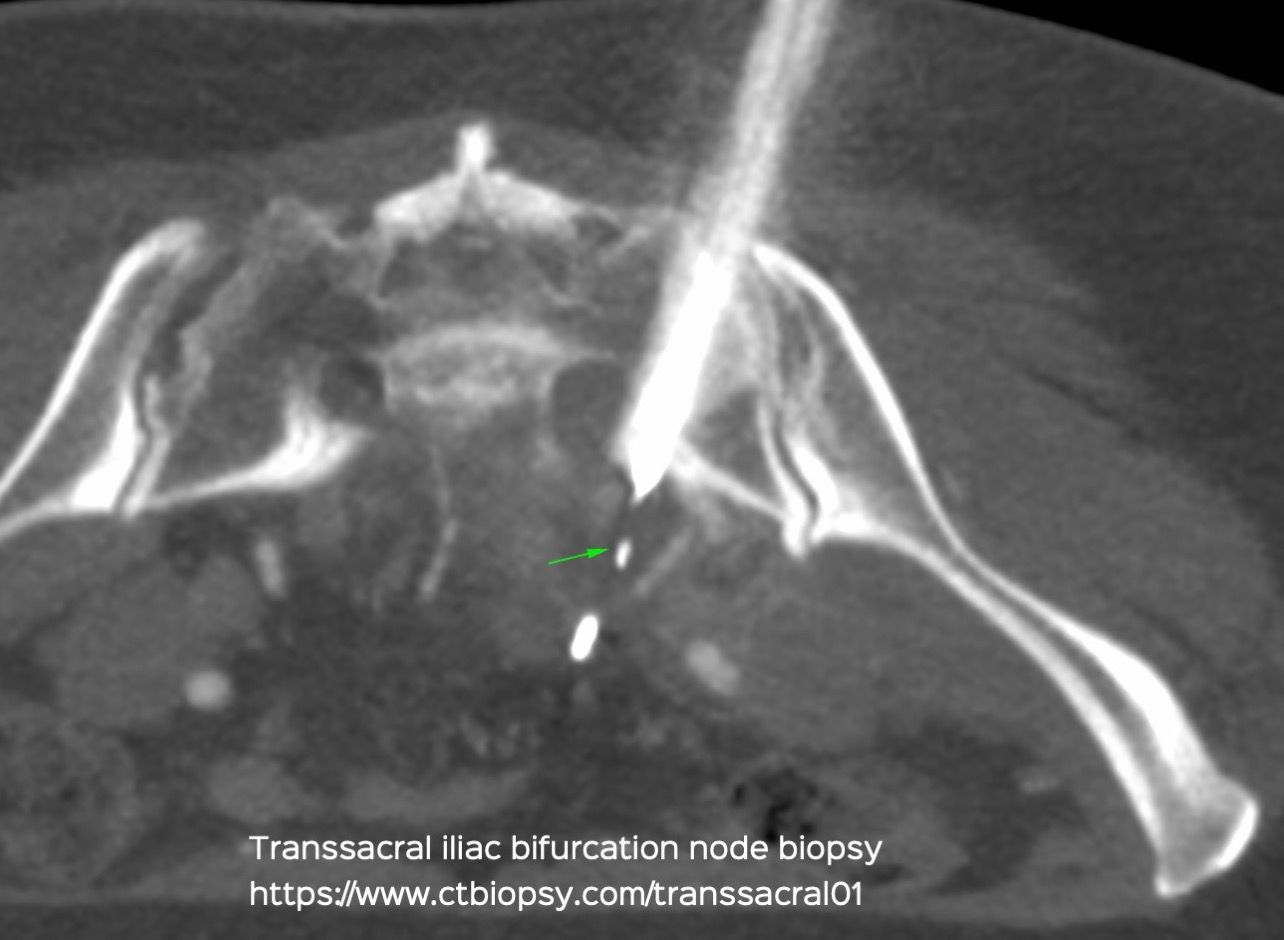

Case 62: Transsacral Biopsy for Iliac Nodes

Bhavin Jankharia - 08 October 2021